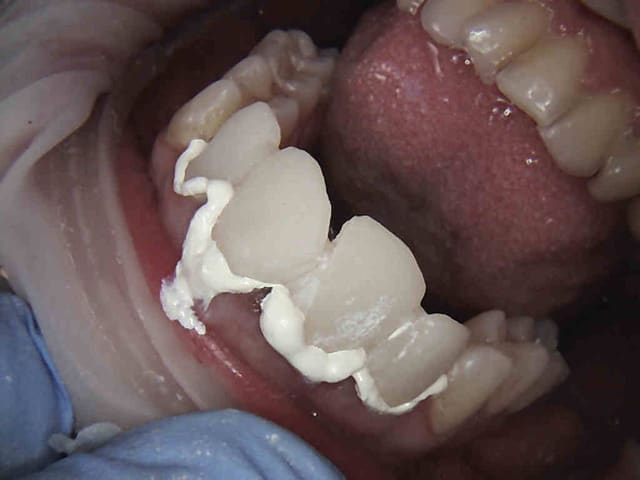

Cas concret ...... en cours pause après 3/4 d'heure. taille à suivre, c'est là ou je chie, ca manque de finesse ! -)))))

Noter le repositionnement des cones , en 2 % c'est impossible.